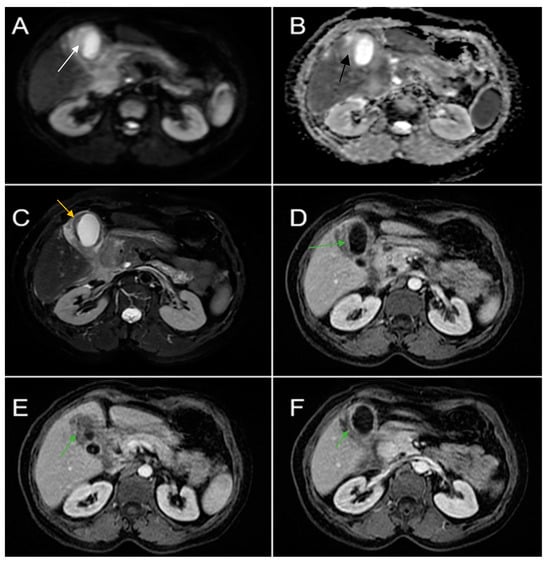

Therefore, clinical suspicion of gallbladder carcinoma was raised and an MRI cholangiography was performed (Figure 3). A laparoscopic cholecystectomy was performed and a subhepatic tumoral block with transvers colon invasion was identified. The patient was referred to the Oncology Department for further specialized treatment and follow-up.

Figure 3. Abdominal MRI sequences highlighting imaging features suggestive of gallbladder carcinoma. (A) Diffusion-weighted imaging (DWI B800) showing bright high signal intensity of the wall thickening of the gallbladder (white arrow). (B) On apparent diffusion coefficient (ADC) map, the wall thickening is dark (black arrow)—illustrating markedly diffusion restriction—which in correlation with increased levels of CEA and CA 19-9 is highly suggestive of gallbladder carcinoma. (C) Axial T2-weighted FIESTA showing asymmetric strongly inhomogeneous wall thickening involving the gallbladder (yellow arrow). (DF). Axial contrast-enhanced T1-weighted images showing heterogeneous enhancement of the wall thickening (green arrows).